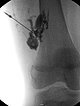

Digitale Subtraktionsangiographie nach Direktpunktion der venösen Malformation während der Sklerosierungsbehandlung. Neben der VM selbst zeigen sich direkte Kommunikationsvenen mit dem tiefen Leitvenensystem. Diese werden mittels Direktpunktion verschlossen mit viskösem Alkohol-Gel.

Röntgendurchleuchtung nach Direktpunktion der venösen Malformation während der Sklerosierungsbehandlung. Durch den Verschluss der Kommunikationsvenen mit dem tiefen Leitvenensystem ist die VM jetzt alleingestellt und kann sklerosiert werden. Nach Anspritzen kein Abstrom des Kontrastmittels mehr in die Leitvenen.